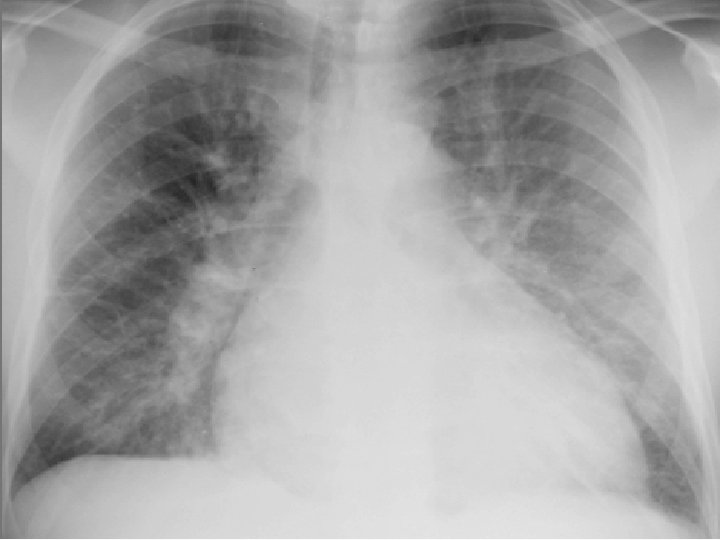

Radiografía de Tórax: Hipertensión Venocapilar Pulmonar: I. - Hilios ensanchados > 15 mm II. - Moteado fino difuso, redistribución apical III. - Líneas B de Kerley, derrames cisurales IV. - Edema alveolar (alas de mariposa)